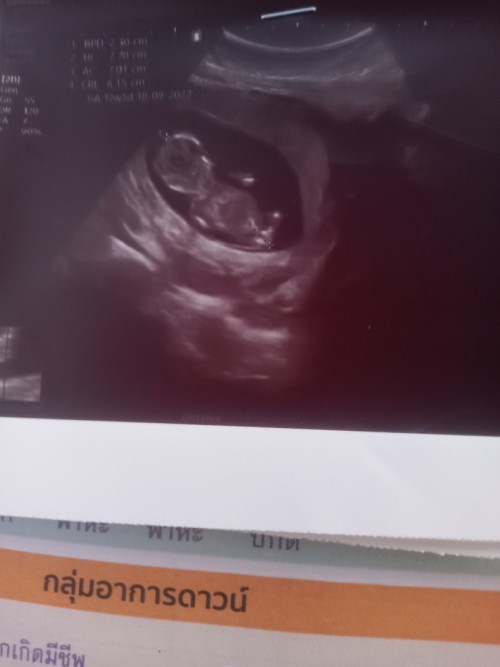

กำหนด29 มิถุนายน65ค่ะ

Post reply image